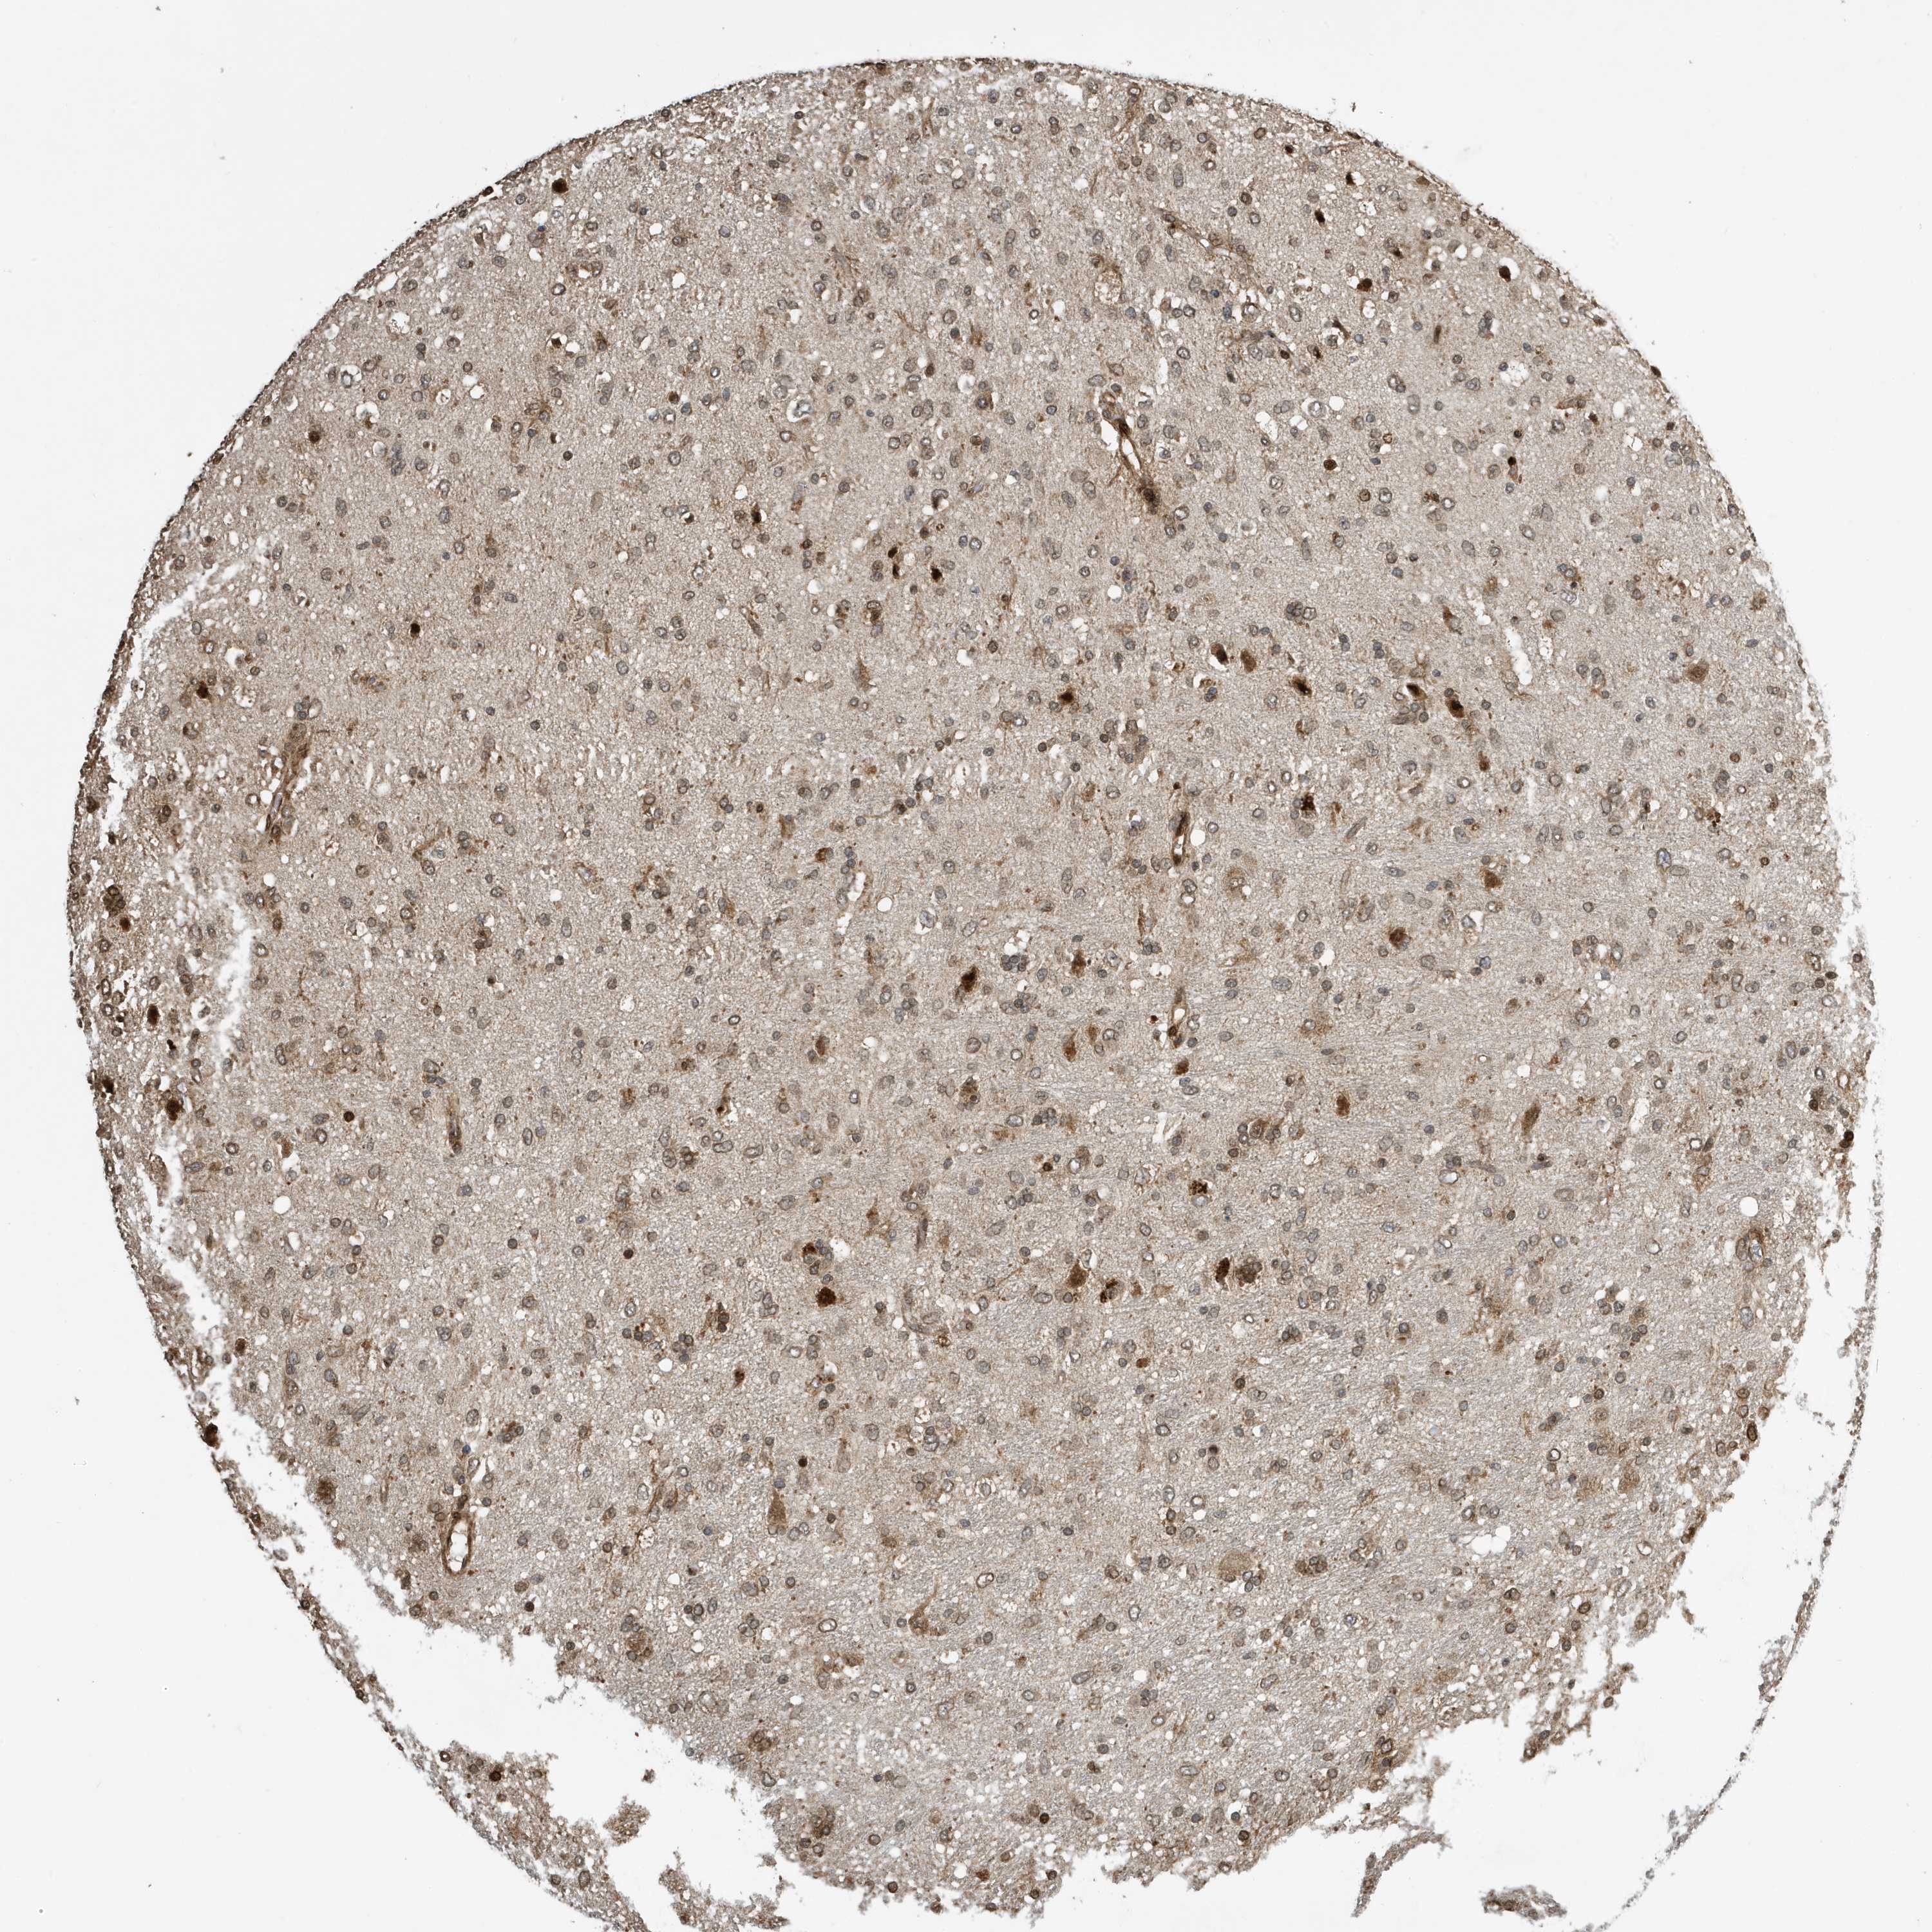

GLIOMA - Protein expressioni

A mouse-over function shows sample information and annotation data. Click on an image to view it in a full screen mode. Samples can be filtered based on level of antibody staining by selecting one or several of the following categories: high, medium, low and not detected. The assay and annotation is described here.

Note that samples used for immunohistochemistry by the Human Protein Atlas do not correspond to samples in the TCGA dataset.

Antibody stainingi

Antibody staining in the annotated cell types in the current human tissue is reported as not detected, low, medium, or high, based on conventional immunohistochemistry profiling in selected tissues. This score is based on the combination of the staining intensity and fraction of stained cells.

Each image is clickable and will lead to virtual microscopy that enables deeper exploration of all samples and also displays staining intensity scores, fraction scores and subcellular localization as well as patient and tissue information for each sample.

Antibody CAB034070

Staining

High

Medium

Low

Not detected

Intensity

Strong

Moderate

Weak

Negative

Quantity

>75%

75%-25%

<25%

None

Location

Nuclear

Cytoplasmic/membranous

Cytoplasmic/membranous,nuclear

Glioma, malignant, High grade

Glioma, malignant, Low grade